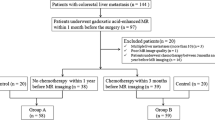

Among 268 patients, 68 patients were excluded because MRI examination was not performed. Among 210 selected patients, 82 patients were excluded for the following reasons: (a) 80 patients had no Gd-EOB MR scans and (b) 2 patients had no MDCT scans less than a 1-month between the two techniques (Fig. 1). Finally, 512 pathologically proven lesions (median 4, range 1–7 per patient), diagnosed as mCRC in 128 patients [72 women-56 men; median age, 58.2 years; range, 33–80 years) comprised our study population. Characteristics of the 128 patients are summarized in Table 1. We also searched the radiological database of our institute during the study period and selected a control group of patients with pathologically proven CRC with subsequent MDCT, Gd-EOB- MR, and ultrasound contrast enhanced study (CEUS); none of the control patients had radiological evidence of liver metastases (as confirmed by at least two techniques) so as to reduce spectrum bias. A total of 46 patients (21 men, 25 women; median age, 56 years [range 33–78 years]) who fit these criteria were enrolled. Characteristics of the 46 patients are also summarized in Table 1.